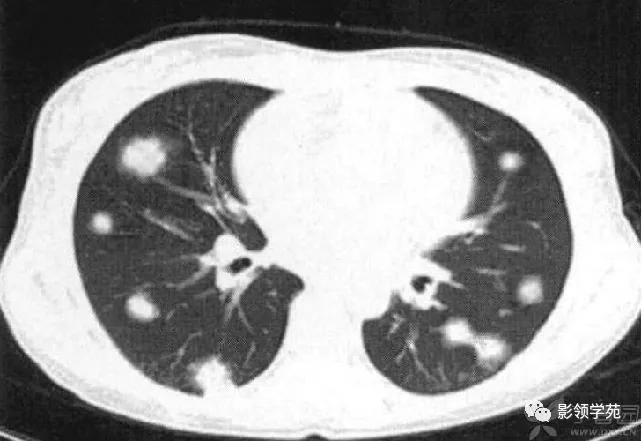

胸部CT检查有阳性发现者占97%,包括多发性肺结节、肿块、楔形病灶、片状浸润阴影、空洞、气道狭窄或溃疡、肺出血等。肺部Wegener肉芽肿CT征象多样,典型的影像学特点是“三多”,即多发性、多样性、多变性。多发性指肺内多处病变,散在双侧肺野,尤以双下肺好发。多样性指病变形态及新旧不一,病变形态多样,呈结节、实变、空洞及条索影等,结节及空洞较为常见。空洞形成是Wegener的重要影像特点,环形空洞是此病的特征。浸润、空洞及结节等多种形式常同时存在。多变性指病变部位、大小及形态处于动态变化之中。

肺内多发结节和肿块是肺Wegener肉芽肿最常见的影像征象,表现为两肺散在分布、多发大小不等类圆形结节或肿块影,以两肺中下野分布多见。部分结节和肿块内可见空洞,洞壁多较厚,内缘光滑或不规则,空洞呈边缘性强化。合并感染时空洞内可形成液-气平面。结节或肿块周围一般都有较短毛刺,部分病灶有长毛刺与邻近的胸膜相连,表现为胸膜凹陷征。这与病理上结节周围存在大量成纤维细胞以及以纤维化形式愈合有关。

病例3:双肺多发结节伴空洞,部分空洞见气液平面。